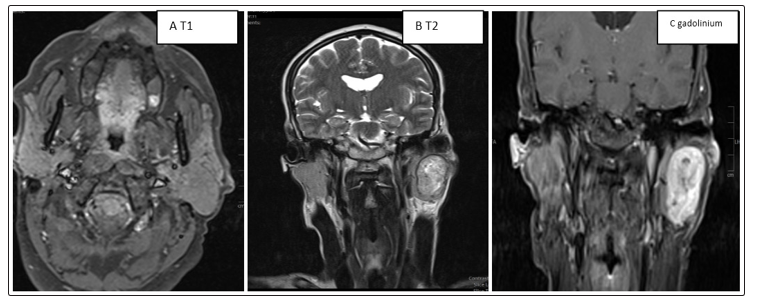

All patients underwent ultrasonography which favored a homogeneous hypoechoic, polyhedogenic formation with posterior reinforcement evoking a pleomorphic adenoma (Table 2) (Figure 1).

Intraparotid image encapsulated in hyposignal in T1 and hypersignal in T2 without locoregional infiltration |

Figure 1: (A, B, C): Intraparotid image encapsulated in hyposignal in T1 and hypersignal in T2